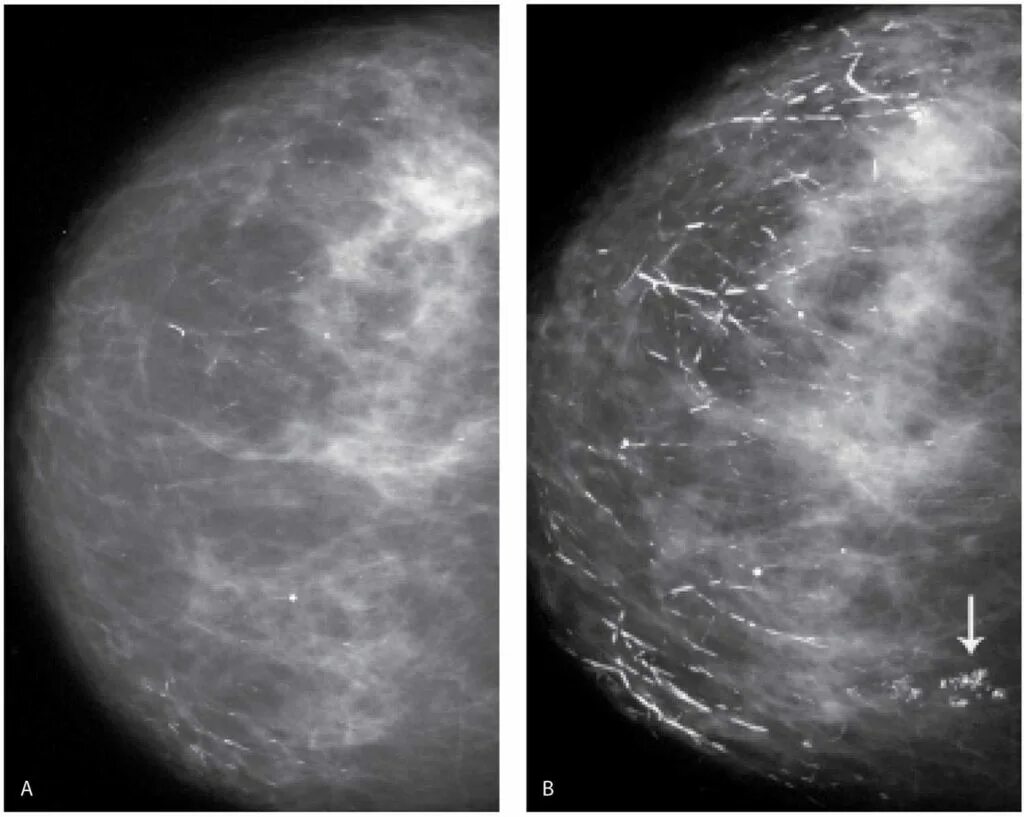

Сгруппированные микрокальцинаты